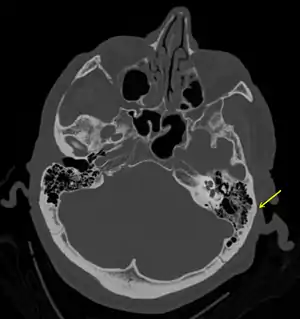

A subtle temporal bone fracture as seen on CT in a person with a severe head injury

A basilar skull fracture as seen on CT

Basilar skull fractures include breaks in the posterior skull base or anterior skull base. The former involve the occipital bone, temporal bone, and portions of the sphenoid bone; the latter, superior portions of the sphenoid and ethmoid bones. The temporal bone fracture is encountered in 75% of all basilar skull fractures and may be longitudinal, transverse or mixed, depending on the course of the fracture line in relation to the longitudinal axis of the pyramid.[5]